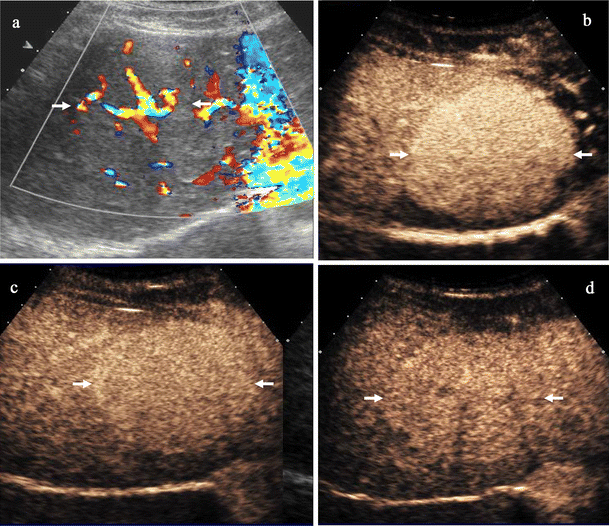

CEUS provides a benign or malignant diagnosis based on focal liver lesion enhancement patter at arterial phase and lesion vascularity at portal—late phase in comparison to the adjacent liver parenchyma (Figs. 1 and 2). Malignancies typically show a low echo-signal intensity at late phase [4, 5, 8], regardless of whether they are hyper- or hypovascular in terms of their arterial supply (Fig. 1). The late phase, with or without hepato-specificity, was showed to be the most important for focal liver lesions characterization since benign lesions present prevalently a sustained enhancement with hyper or isovascular appearance to the adjacent liver while malignant lesions present prevalently microbubble washout with hypovascular appearance [115] (Fig. 2).

a-d Focal nodular hyperplasia in a 45-year-old woman. a Colour Doppler. Central spoke wheel-shaped pattern (arrows). b-d CEUS. Contrast specific mode: Cadence Contrast Pulse Sequencing after sulphur hexafluoride-filled microbubble injection with low transmit power insonation. Diffuse homogeneous enhancement with hypervascular appearance is evident at arterial phase (arrows) b, persisting at portal c and late phase d with lesion (arrows) isovascularity to the adjancent liver parenchyma